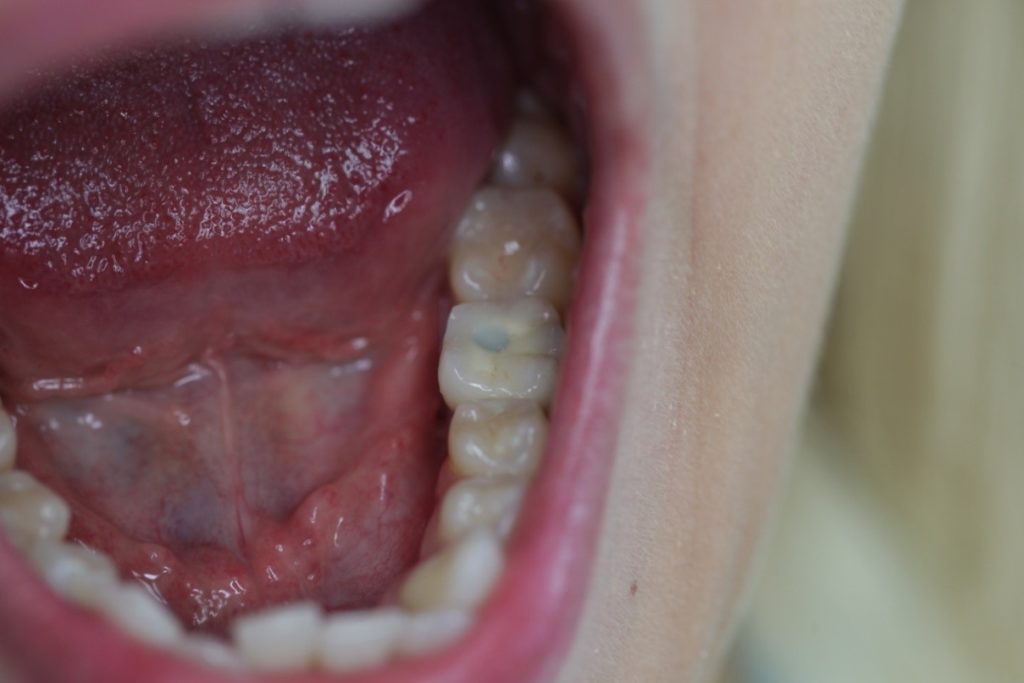

Screw-retained implant crown secured on the lower left first molar in the mouth sealed with a permanent, white composite filling.

On top of screw-retained crowns a small slot guides the through bolt securing the crown in the implant. Once the screw is in place the slot is sealed with an aesthetic composite filling. Unfortunately this filling does not always seal perfectly. Occasionally the slot is visible to a minor extent, but only to those “in search of” an aesthetic fault. Under normal circumstances the minor colour transition of the filling is indistinguishable during speech or laughter.